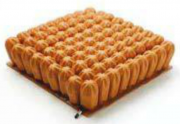

| 08:48, 23 במאי 2013 | משטחלחץ2.png (קובץ) |  |

| 08:09, 23 במאי 2013 | משטחלחץ1.png (קובץ) |  |